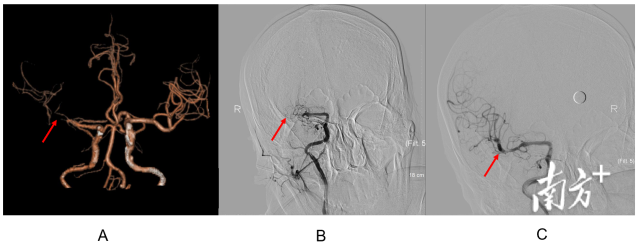

头颈部CTA和脑血管造影结果提示冯先生右侧大脑中动脉次全闭塞(图A和B箭头处),经过介入取栓、植入支架后,血管再通(图C箭头处)。